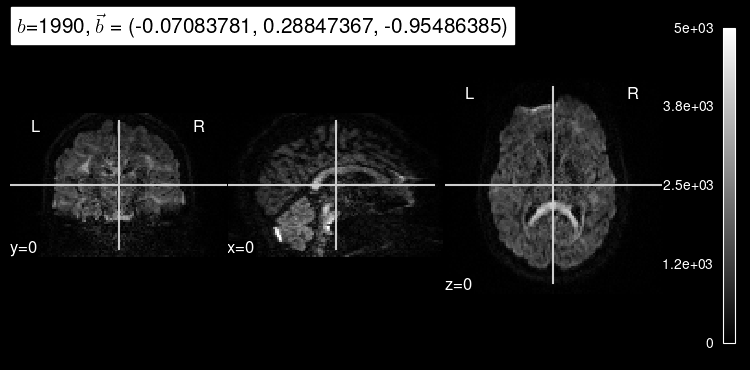

We can also get some insight into how a particular diffusion-weighted orientation looks like by selecting them with the argument index

.

dmri_dataset.plot_mosaic(index=100, vmax=5000);

Diffusion that exhibits directionality in the same direction as the gradient results in a loss of signal. As we can see, diffusion-weighted images consistently drop almost all signal in voxels filled with cerebrospinal fluid because there, water diffusion is free (isotropic) regardless of the direction that is being measured.

We can also see that the images at index=10

and index=100

have different gradient strength (”b-value”).

The higher the magnitude of the gradient, the more diffusion that is allowed to occur, indicated by the overall decrease in signal intensity.

Stronger gradients yield diffusion maps with substantially lower SNR (signal-to-noise ratio), as well as larger distortions derived from the so-called “Eddy-currents”.